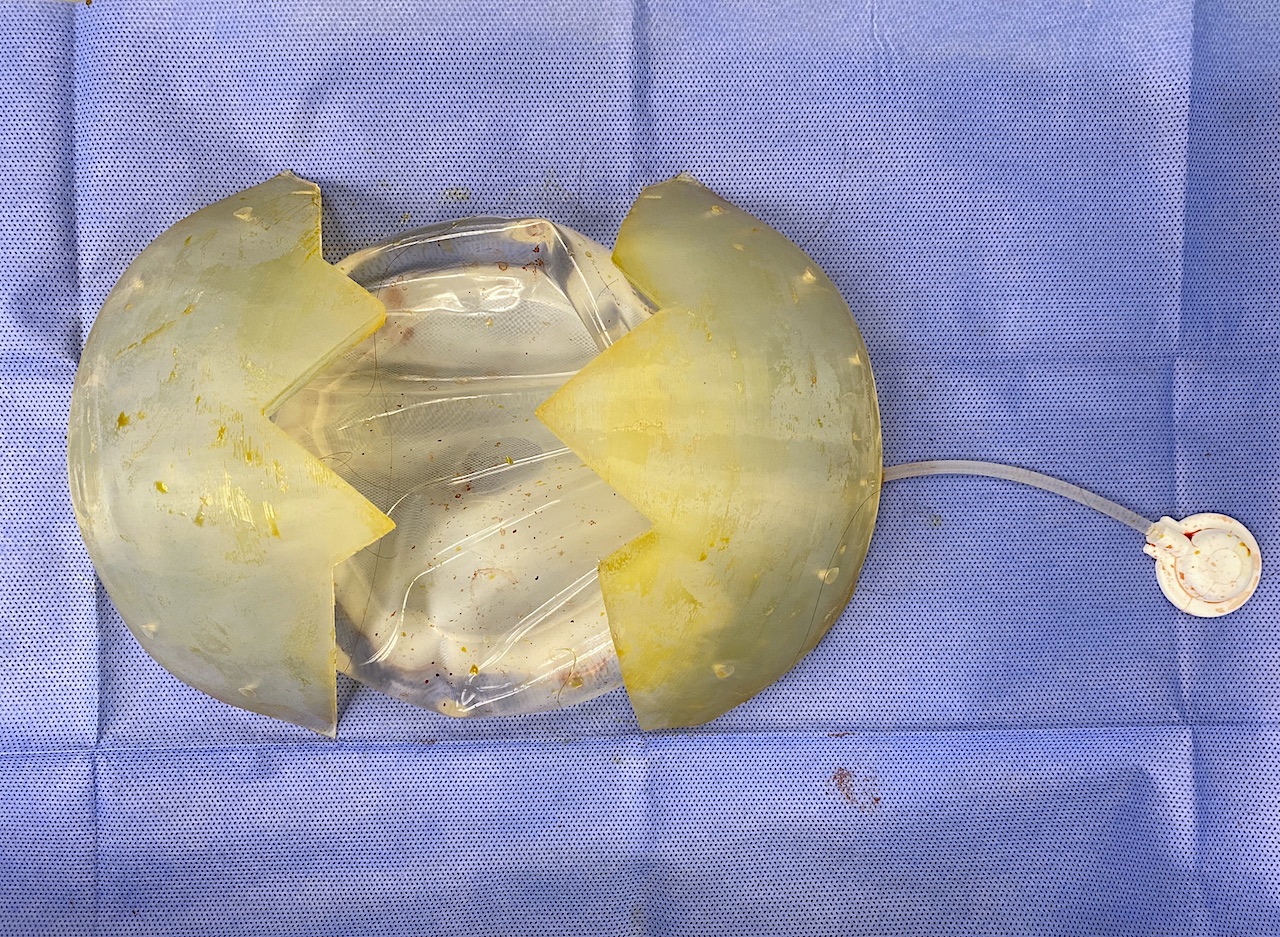

Desire for large overall skull augmentation procedure. Two piece custom skull implant designed with 250ccs volume.

1st stage scalp expander placed and inflated to 225ccs. 2nd stage two piece skull implant placed 4 months later.

Desire for large overall skull augmentation procedure. Two piece custom skull implant designed with 250ccs volume.

1st stage scalp expander placed and inflated to 225ccs. 2nd stage two piece skull implant placed 4 months later.